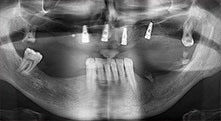

Bratu: Wir nutzen die Instrumente routinemäßig für die Entnahme von Knochenblöcken und das Spalten von Kieferkämmen. Weiterhin osteotomieren wir mit den Piezomed B6/B7 retinierte Zähne und entfernen nicht erhaltungsfähige Implantate. Alles Indikationen, bei denen es auf tiefe, saubere Schnitte ankommt.

Bratu: Wir augmentieren im seitlichen Unterkiefer gern mit der Sandwich-Technik. Dabei wird ein Knochendeckel mit der Piezosäge präpariert und das krestale Fragment mit Mikroschrauben fixiert. Dazwischen platzieren wir eine Mischung aus autologem Knochen und xenogenem Knochenersatzmaterial. Das funktioniert sehr zuverlässig. Bei Kieferkammspaltungen im Unterkiefer sollten Sie nie auf ausreichend dimensionierte vertikale Schnitte verzichten. Sonst kann der Knochen leicht frakturieren.

Bratu: Ich halte Piezo für einen großen Sprung nach vorn für die Oralchirurgie. Die Technik macht Knochenpräparationen sicherer und leichter. Man verliert wenig Knochen, zum Beispiel bei Extraktionen. In der ästhetischen Zone ist dies sehr wichtig, vor allem wenn eine Sofortimplantation geplant ist. Auch für Weichgewebe ist Piezochirurgie ein Sicherheitsgewinn: Membranverletzungen in der Kieferhöhle sind im Prinzip Geschichte, ebenso Nervverletzungen bei Knochenblockentnahmen. Es gibt auch Daten, die geringere postoperative Schwellung und Beschwerden zeigen. Übrigens lassen sich mit Piezochirurgie auch sehr gut Kieferhöhlensepten präparieren. Nicht zuletzt profitieren unsere Patienten von der schonenden Arbeitsweise dieser Technik.